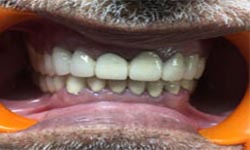

(9) Metal Ceramic Crowns

Before Treatment

After Treatment

Mr. Shiv Narayan Singh,aged 78yrs, came with a concern of multiple broken and mobile teeth with difficulty in chewing food. So, multiple RCTs followed by metal-ceramic crowns were delivered to the patient ,restoring his beautiful smile.